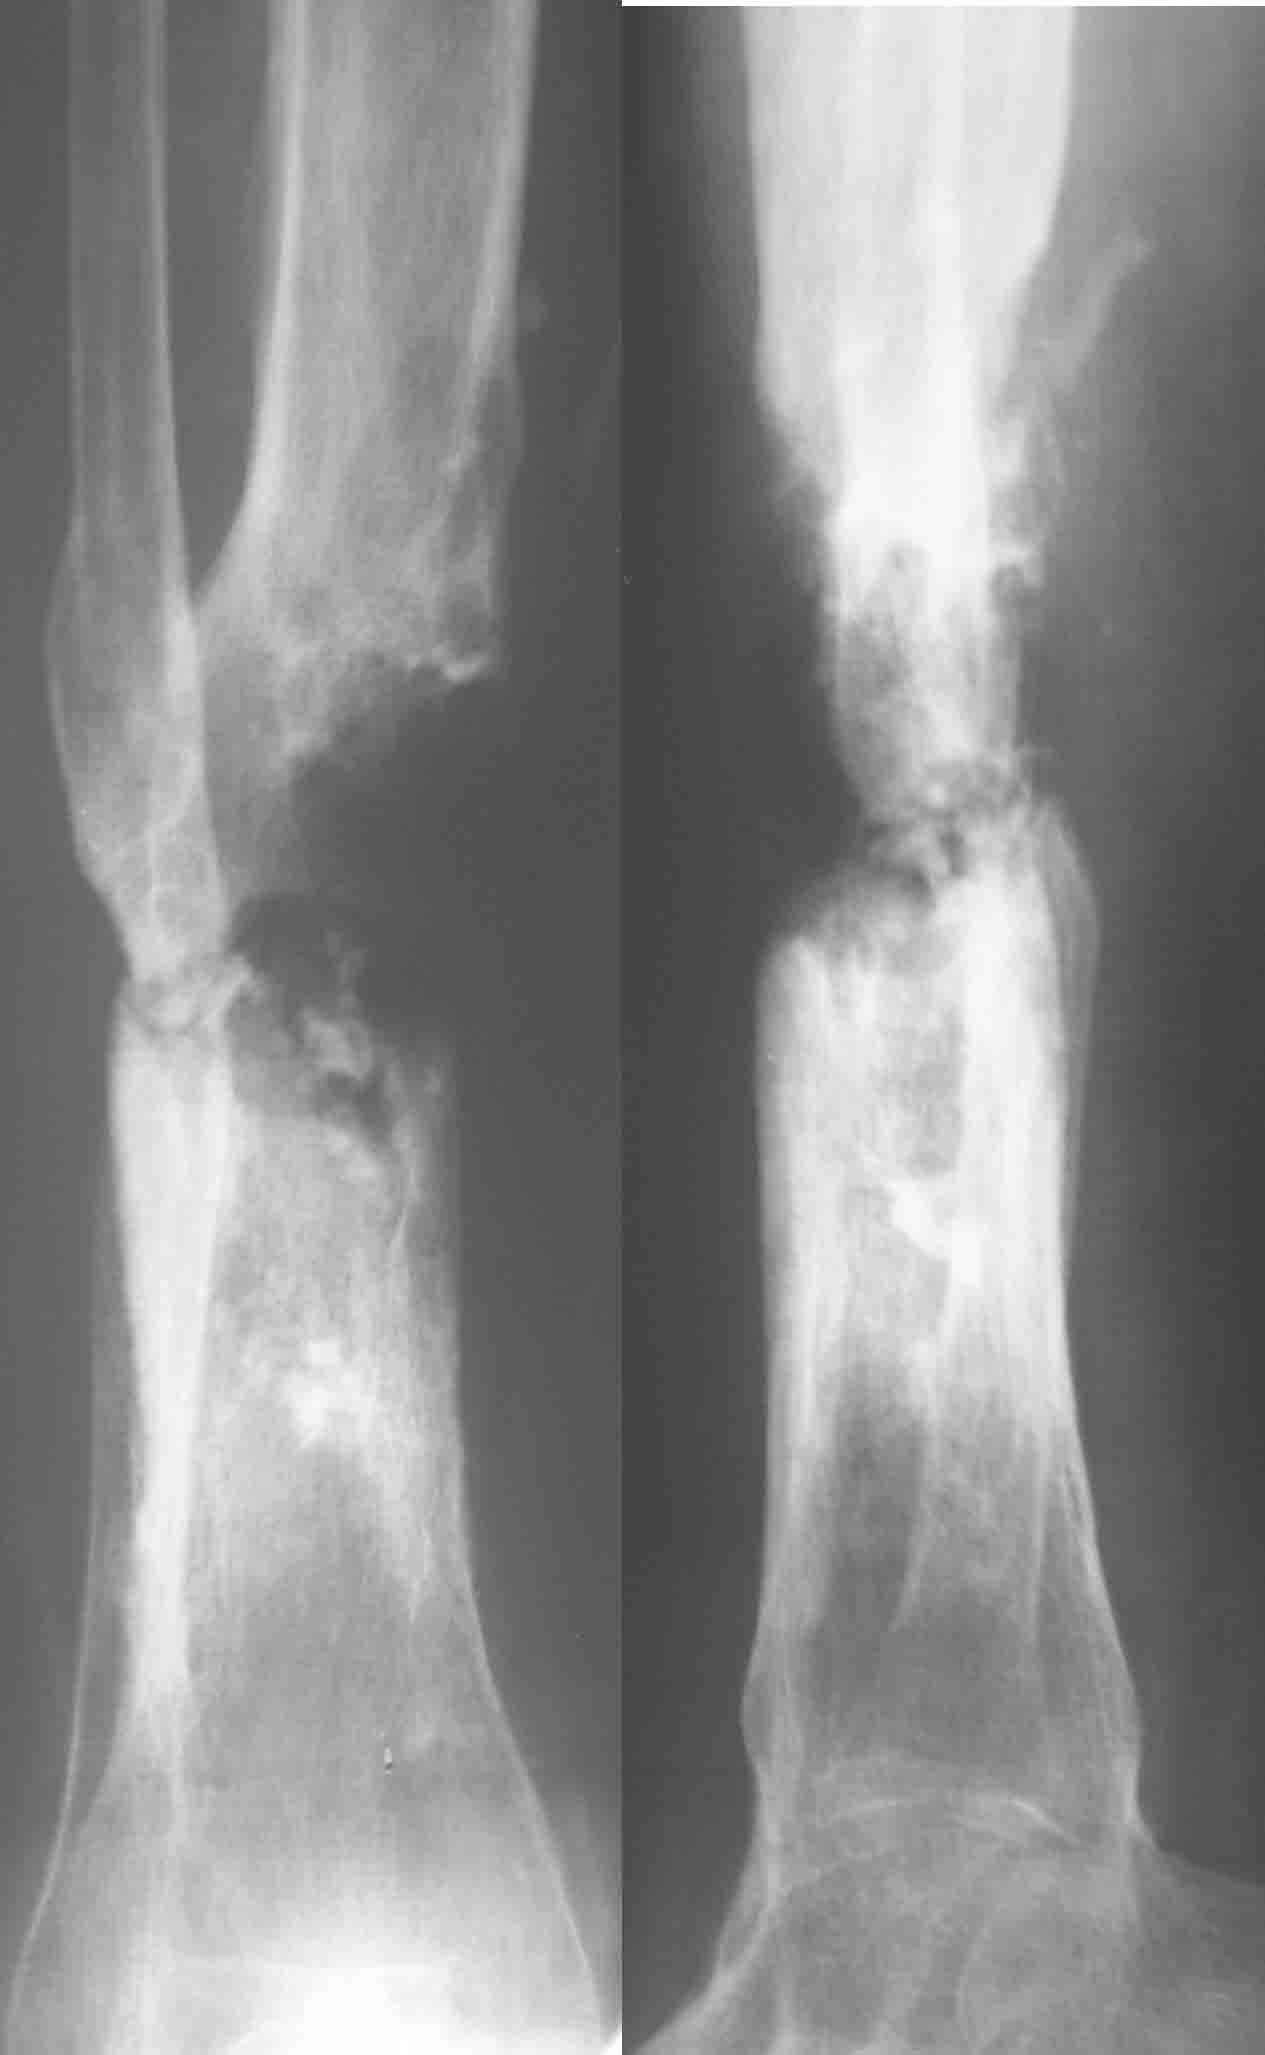

Итак, в настоящий момент больной пришел к нам с полной нагрузкой на оперированную конечность и с такой картиной (см. приложение). Участок мягких тканей с передней стенкой нижней трети ББК, выгнил и представляет дефект 2×2,5 см. На перевязке - циркулярный(?) некроз костной трубки.

Сегментарного некроза не видно. Есть только краевой дефект спереди, задняя стенка вполне хорошая, и со стержнем есть условия для ее утолщения со временем. Так что проблему должна решить местная санация (если доступно, использовать VAC). Если грануляции не закроют все, что надо закрыть, придется делать пластику полнослойным лоскутом. Идеально бы - с микроососудистым анастомозом.

Позволю высказать свое мнение. У меня есть сомнения, что задняя стенка большеберцовой кости осталась "здоровой". Если после первой операции костная ткань и могла остаться частично жизнеспособной, то развившаяся гнойная инфекция наверняка способствовала окончательному некрозу кости.

Я бы, наверное, после удаления штифта сосредоточился на определения жизнеспособности кости по задней поверхности. Если будут сомнения, то я бы сделал резекцию.

Тогда можно рассмотреть вопрос одновременного удаления штифта, мышечной (в данной области применим проксимально отсеченный лоскут камбаловидной мышцы) или микрохирургической (что более надежно) пластики дефекта мягких тканей, остеотомии проксимального фрагмента большеберцовой кости, остеосинтеза блокируемым штифтом с а/б покрытием, наложения простого аппарата Илизарова (можно из полуколец) для дистракции на штифте. При данном варианте пациент сохраняет возможность полной опоры на ногу, что очень важно для заживления у пожилого пациента) и отпадает необходимость в проведении дополнительный операций (при благоприятном развитии событий).

Выкладываю картинки похожей пациентки. Извините, что без окончательных снимков (сейчас их нет под рукой). Правда мы имели проблемы у данной больной после снятия аппарата, когда промежуточный фрагмент большеберцовой кости сместился на 1,5 см дистально и отошел от проксимальной части кости. До сих пор у пациентки на снимках определяется лишь тонкая полоска кости по задней поверхности за штифтом (образовалось что-то вроде маленького регенерата)в области стыковки промежуточного и проксимального фрагментов. Больная пока решила подождать. Не хочет оперироваться, так как ходит не хромая, работает.